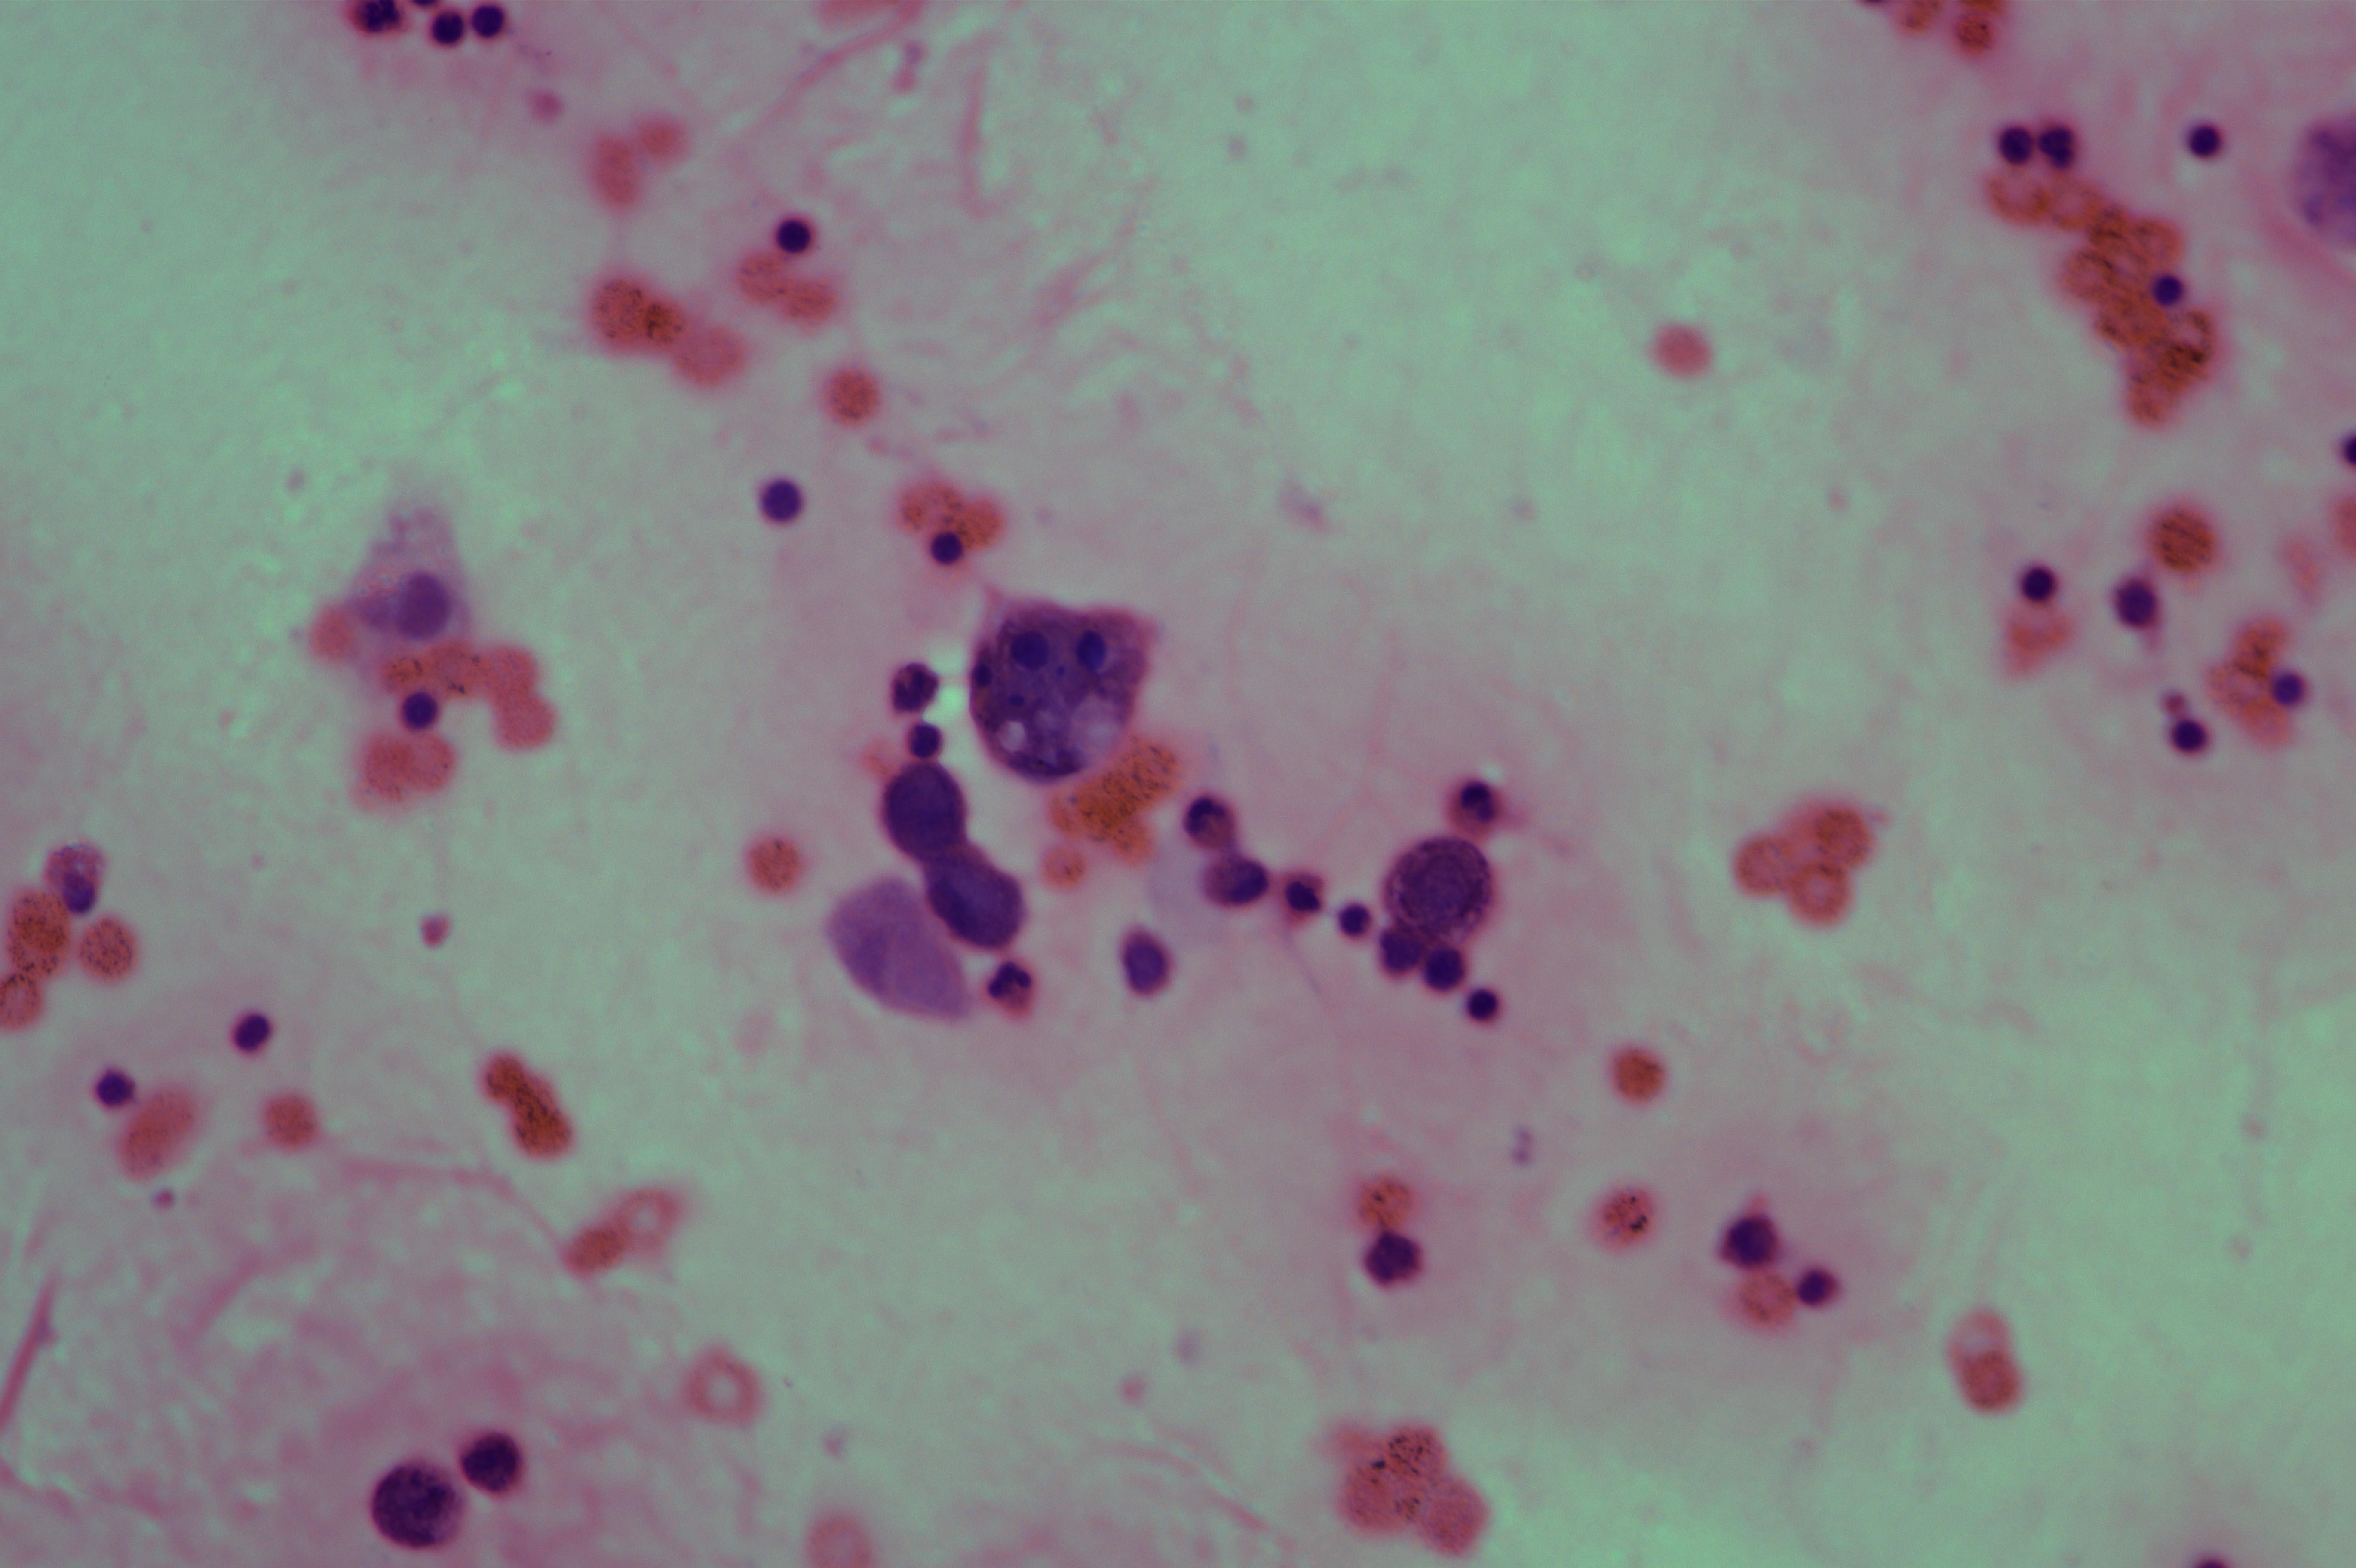

女,78岁,胸水腺癌

性别

女

年龄

78岁

一般病史

胃低分化腺癌术后一年

标本类型

胸水

制片方法

涂片

染色方法

HE

图3

考虑为腺癌

图3、图9是什么?